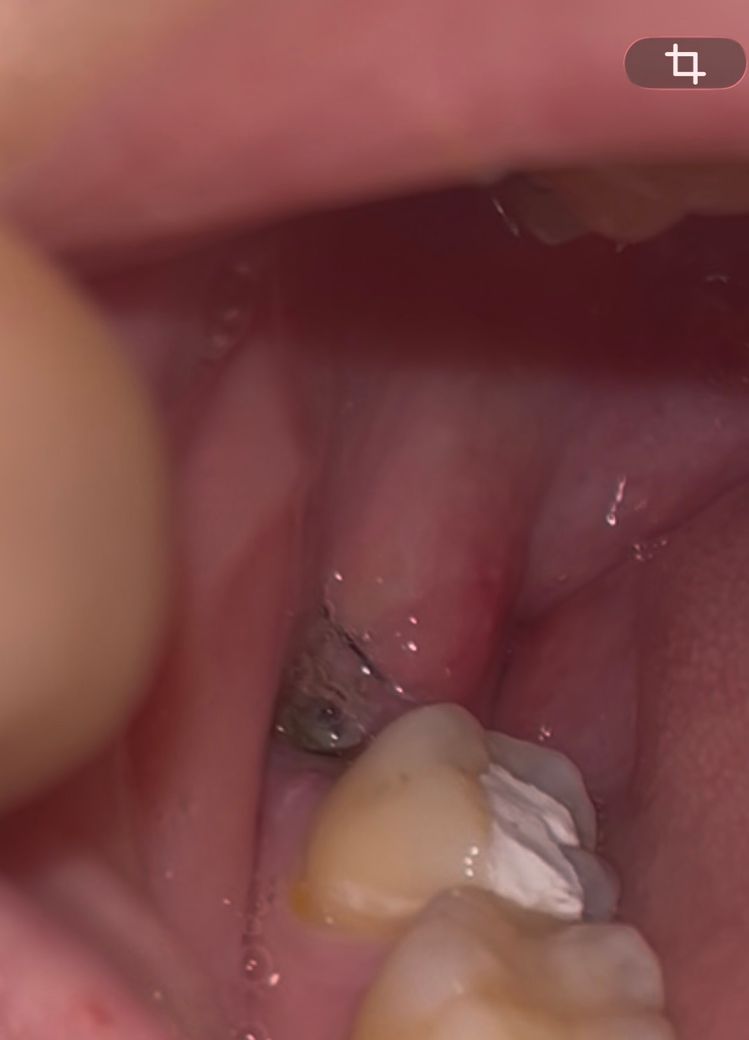

어제 사랑니 뽑았는데 드라이소켓일까요?ㅠㅠ

어제 저녁에 사랑니 뽑았는데요

지혈이 거의 6시간 동안 안 됐어서 거즈 계속 갈면서 겨우 지혈시키고 잤거든요

방금 확인해보니까 혈병이 하나도 안 생겨있고 색이 좀 초록색?처럼 돼있는데 드라이소켓 가능성 있을까요?

발치 후 3~5일차쯤 통증이 심해지는 거로 알고있는데 전조증상일까봐 걱정됩니다ㅜㅜ

지금은 통증이 아예 없어요

사진으로 봤을 경우에는 드라이소켓으로 보이지는 않습니다. 드라이 소켓이 생겼을 경우에는 통증이 심하고 악취가 나기 때문입니다.

드라이소켓은 한국말로 하면 건성치조와입니다. 발치한 부위가 텅 비어 뼈와 신경부가 노출되어 있는겁니다. 지금으로선 드라이소켓이라고 볼 수 없습니다.